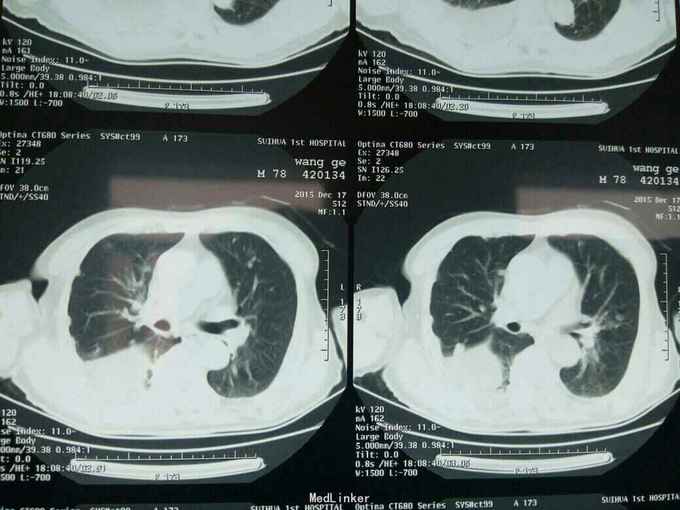

根据病史查体诊断:腰间盘突出症待确诊。应用消肿营养神经镇痛治疗。一天。查核磁共振示:腰椎多节段间盘突出伴椎管狭窄。第二腰椎骨破坏侵及椎板。部分突入椎管,脊髓受压。诊断:腰间盘突出伴椎管狭窄。第二腰椎转移癌,脊髓受压。经与家属沟通,查双肺CT:双肺下叶炎症。肺部纤维化。可见肿瘤阴影。肋骨及胸膜受累。胸椎部分骨破坏。最终诊断:双肺癌,胸椎,腰椎骨转移,脊髓受压。多节段腰椎间盘突出。病人至肿瘤科治疗。